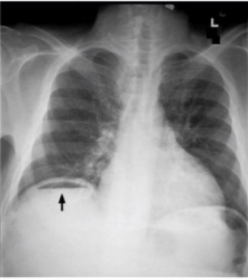

describe perforated ulcers

A

• sudden and severe pain in the abdomen

• board-like rigidity of the abdomen

• abnormal finding of “free air” under the diaphragm

• if ulcer has perforated into a surrounding vessel then excessive bleeding may cause hemodynamic compromise